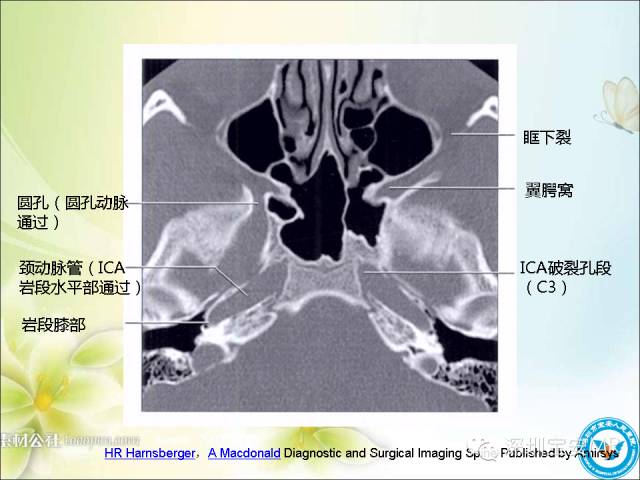

【PPT】颈内动脉颅内段影像解剖(附临床血管病例)